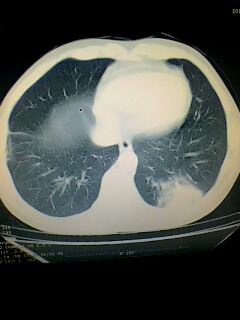

考虑左肺下叶周围型肺癌.图象欠清,请问病人贵更?

考虑左肺下叶周围型肺癌.

图像资料欠清,建议强化,考虑周围型肺癌。

左下肺肿块影,深分叶,考虑肺癌。

左下肺球形病灶,考虑:1:球形肺炎;2:周围型肺癌不除外,建议治疗后复查

不排除左肺下叶周围型肺癌可能!建议穿刺活检!

考虑左肺下叶周围型肺癌。

考虑左肺下叶周围型肺癌并阻塞性肺炎。